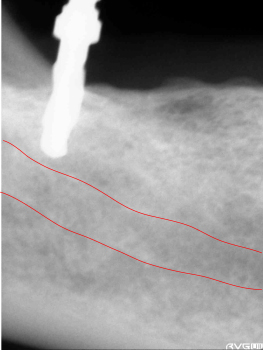

下歯槽管まで、近くなった所で安全性を確認するためレントゲン写真を撮影しまだ余裕があるのを確認します。 | ||